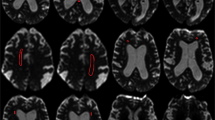

Mean T1 values of the cerebrum were obtained by manually drawing the predefined periventricular regions of interest (ROI) on two axial sections: first was at the level of the internal capsule (four ROIs: A1 right inferior anterior horn; A2 left inferior anterior horn; A3 right inferior posterior horn; A4 left inferior posterior horn) and second at the superior level, on which both lateral ventricles were fully visible (six ROIs: B1 right superior anterior horn; B2 left superior anterior horn; B3 right corona radiata; B4 left corona radiata; B5 right superior posterior horn; B6 left superior posterior horn). A representative case with all ROIs is given in Fig. 1. The ROIs were drawn on gray scale T1 maps without artificial color borders and using corresponding T2-weighted anatomical images. To demonstrate inter-rater reliability, a second T1 mapping experienced rater manually determined the predefined ROIs on all baseline T1 maps and the mean T1 relaxation times were compared to the first rater.

Representative T1 maps of an iNPH case demonstrating the predefined regions of interest (ROIs). a Four ROIs manually drawn at the level of the internal capsule (a1 right inferior anterior horn; a2 left inferior anterior horn; a3 right inferior posterior horn; a4 left inferior posterior horn) and b six ROIs drawn at the superior level, on which both lateral ventricles were fully visible (b1 right superior anterior horn; b2 left superior anterior horn; b3 right corona radiata; b4 left corona radiata; b5 right superior posterior horn; b6 left superior posterior horn). The mean T1 relaxation times were analyzed for every ROI

Representative cases demonstrating the ROI selection and qualitative differences in color-coded T1 maps are shown in Figs. 1 and 2. On baseline scans, T1 relaxation times in all ROIs were higher in iNPH patients compared to controls with highest differences found in the inferior anterior horn (1006.1 ± 93.1 ms vs. 911.4 ± 77.4 ms; p = 0.023, ∆T1 = 94.7 ms) and the superior posterior horn (982.9 ± 103.1 ms vs. 892.5 ± 68 ms; p = 0.037, ∆T1 = 90.4 ms) of the lateral ventricles (see Table 2 and Fig. 3).